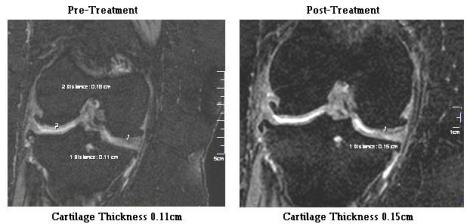

* This is for assessment by a radiologist